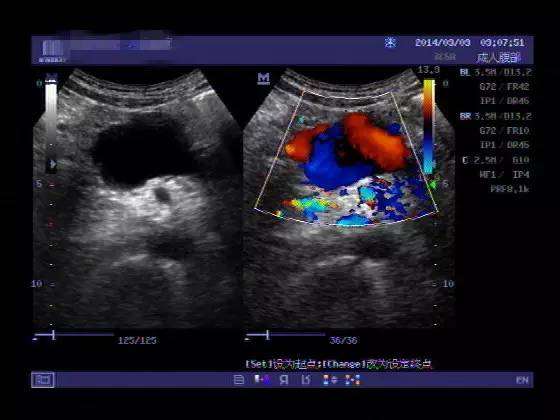

多普勒超声

无创、易行的检查,可明确有无腹主动脉瘤,以及瘤体的部位和大小。所以彩超对筛查、定期视察、术后的病人的随访非常有价值。医博士建议65岁以上老人可通过超声进行腹主动脉瘤筛查,而家族中有腹主动脉瘤史的亲属则宜50岁开始进行筛查。